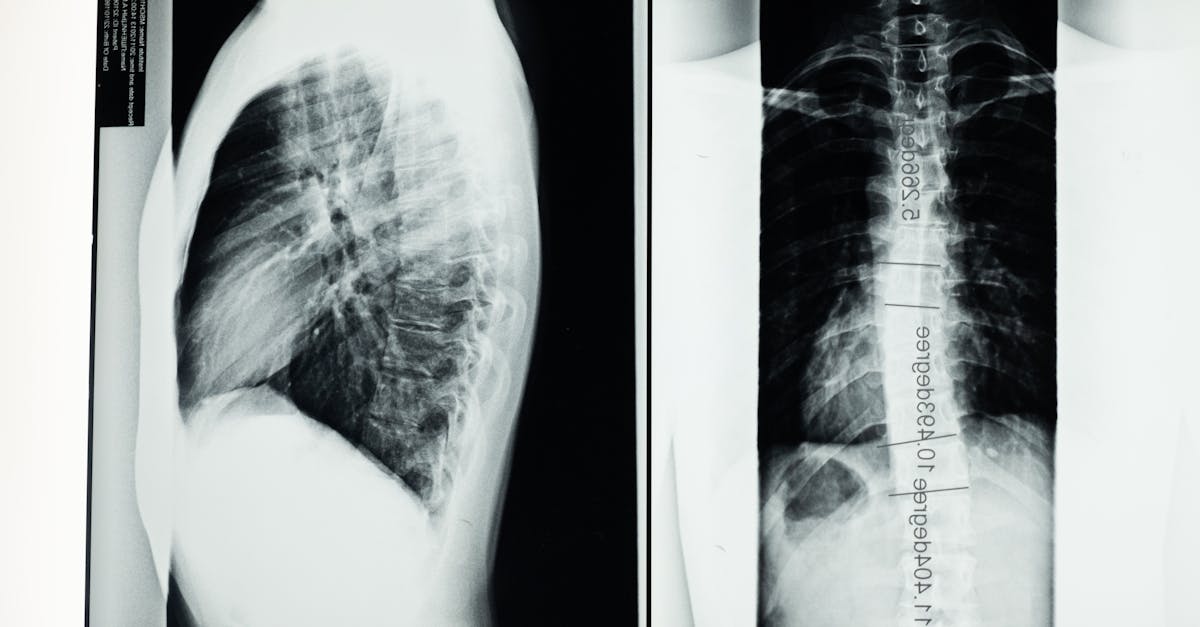

Comprendre la sténose spinale

La sténose spinale est une condition caractérisée par un rétrécissement du canal rachidien, entraînant une compression des nerfs et de la moelle épinière. Cela peut provoquer des douleurs lombaires, des engourdissements, ainsi que des difficultés à marcher. Les symptômes peuvent varier d’une personne à l’autre et sont souvent exacerbés par des activités physiques. Comprendre cette pathologie est crucial pour envisager des options de traitement pertinentes, parmi lesquelles la décompression neurovertébrale apparaît comme une solution non invasive.

La décompression neurovertébrale est une méthode thérapeutique non invasive qui a gagné en popularité ces dernières années, notamment pour son rôle protecteur contre les récidives de la sténose spinale. Cette condition, souvent caractérisée par un rétrécissement du canal spinal, entraîne une compression sur la moelle épinière et les nerfs environnants, causant ainsi des douleurs et des limitations fonctionnelles. La décompression neurovertébrale s’avère être une approche prometteuse dans la gestion de ces symptômes, en ciblant les causes profondes du problème.

Développée pour soulager la pression sur la colonne vertébrale, la décompression neurovertébrale utilise des tables spécialisées pour étirer la colonne de manière contrôlée. Cela permet de réduire la pression sur les disques intervertébraux et d’améliorer le flux sanguin vers les zones touchées. Cette technique offre une alternative naturelle, évitant les interventions chirurgicales invasives et les traitements médicamenteux qui présentent souvent des effets secondaires indésirables.